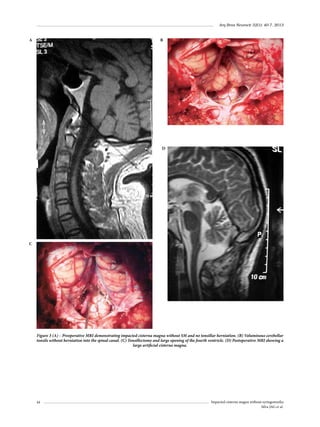

lacerated intracranial internal carotid arteries – case report.

Neurol Med Chir (Tokyo). 2006;46(2):84-7.

Kawaguchi T, Kawano T, Kaneko Y, Ooasa T, Ooigawa H,

Ogasawara S. Traumatic lesions of the bilateral middle

meningeal arteries – case report. Neurol Med Chir (Tokyo).

2002;42(5):221-3.